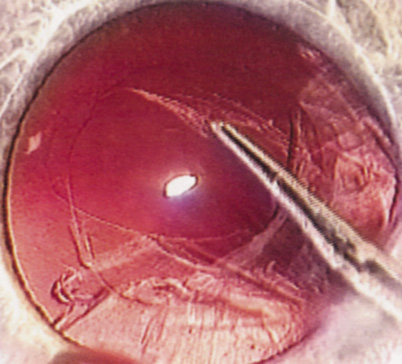

Patients who complain of glare from point sources of light, such as oncoming headlights or bright sunshine, may be best evaluated by a different form of glare testing. To simulate the environment of the patients' symptoms, Snellen acuity is measured while directing a point source of light obliquely toward the eye outside their best spectacle correction or outside of a phoropter dialed in with their best manifest refraction (Fig. 2).